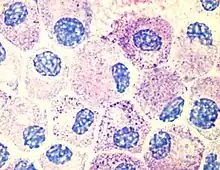

One of the most outstanding results of his dissertation investigations was the discovery of a new cell type. Ehrlich discovered in the protoplasm of supposed plasma cells a granulate which could be made visible with the help of an alkaline dye. He thought this granulate was a sign of good nourishment, and accordingly named these cells mast cells, (from the German word for an animal-fattening feed, Mast). This focus on chemistry was unusual for a medical dissertation. In it, Ehrlich presented the entire spectrum of known staining techniques and the chemistry of the pigments employed. While he was at the Charité, Ehrlich elaborated upon the differentiation of white blood cells according to their different granules. A precondition was a dry specimen technique, which he also developed. A drop of blood placed between two glass slides and heated over a Bunsen burner fixed the blood cells while still allowing them to be stained. Ehrlich used both alkaline and acid dyes, and also created new "neutral" dyes. For the first time this made it possible to differentiate the lymphocytes among the leucocytes (white blood cells). By studying their granulation he could distinguish between nongranular lymphocytes, mono- and poly-nuclear leucocytes, eosinophil granulocytes, and mast cells.